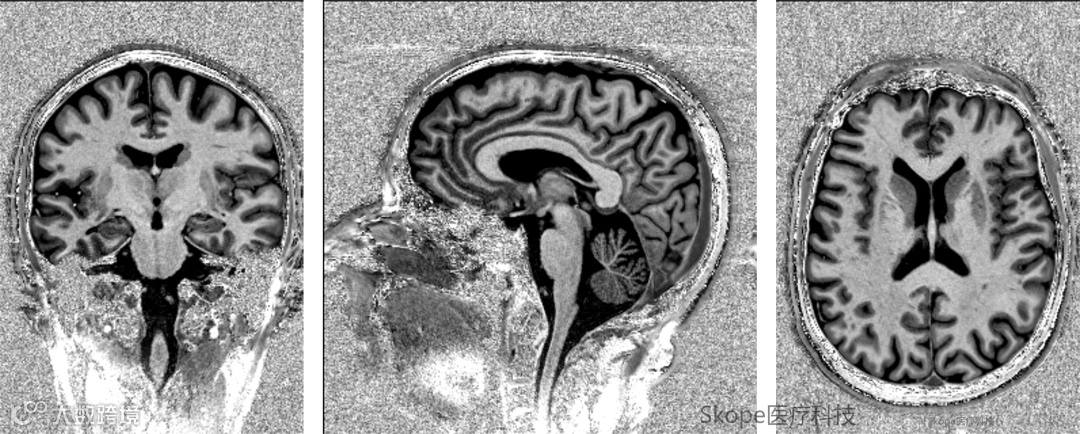

NeuroCam™ 7T多序列成像效果

T2 TSE、MP2RAGE、FLAIR等是高场MRI中常用的结构成像序列,它们在神经系统疾病的诊断中扮演着关键角色。为了充分发挥7T超高场的优势,精确呈现脑部精细结构和深部病变,这些序列对图像的信号一致性和组织间对比度有着极高的标准。

通过下列实际成像,直观感受多通道接收与pTx发射所带来的更高的组织边界清晰度、更均匀的信号分布,以及更完整的结构呈现。

MP2RAGE